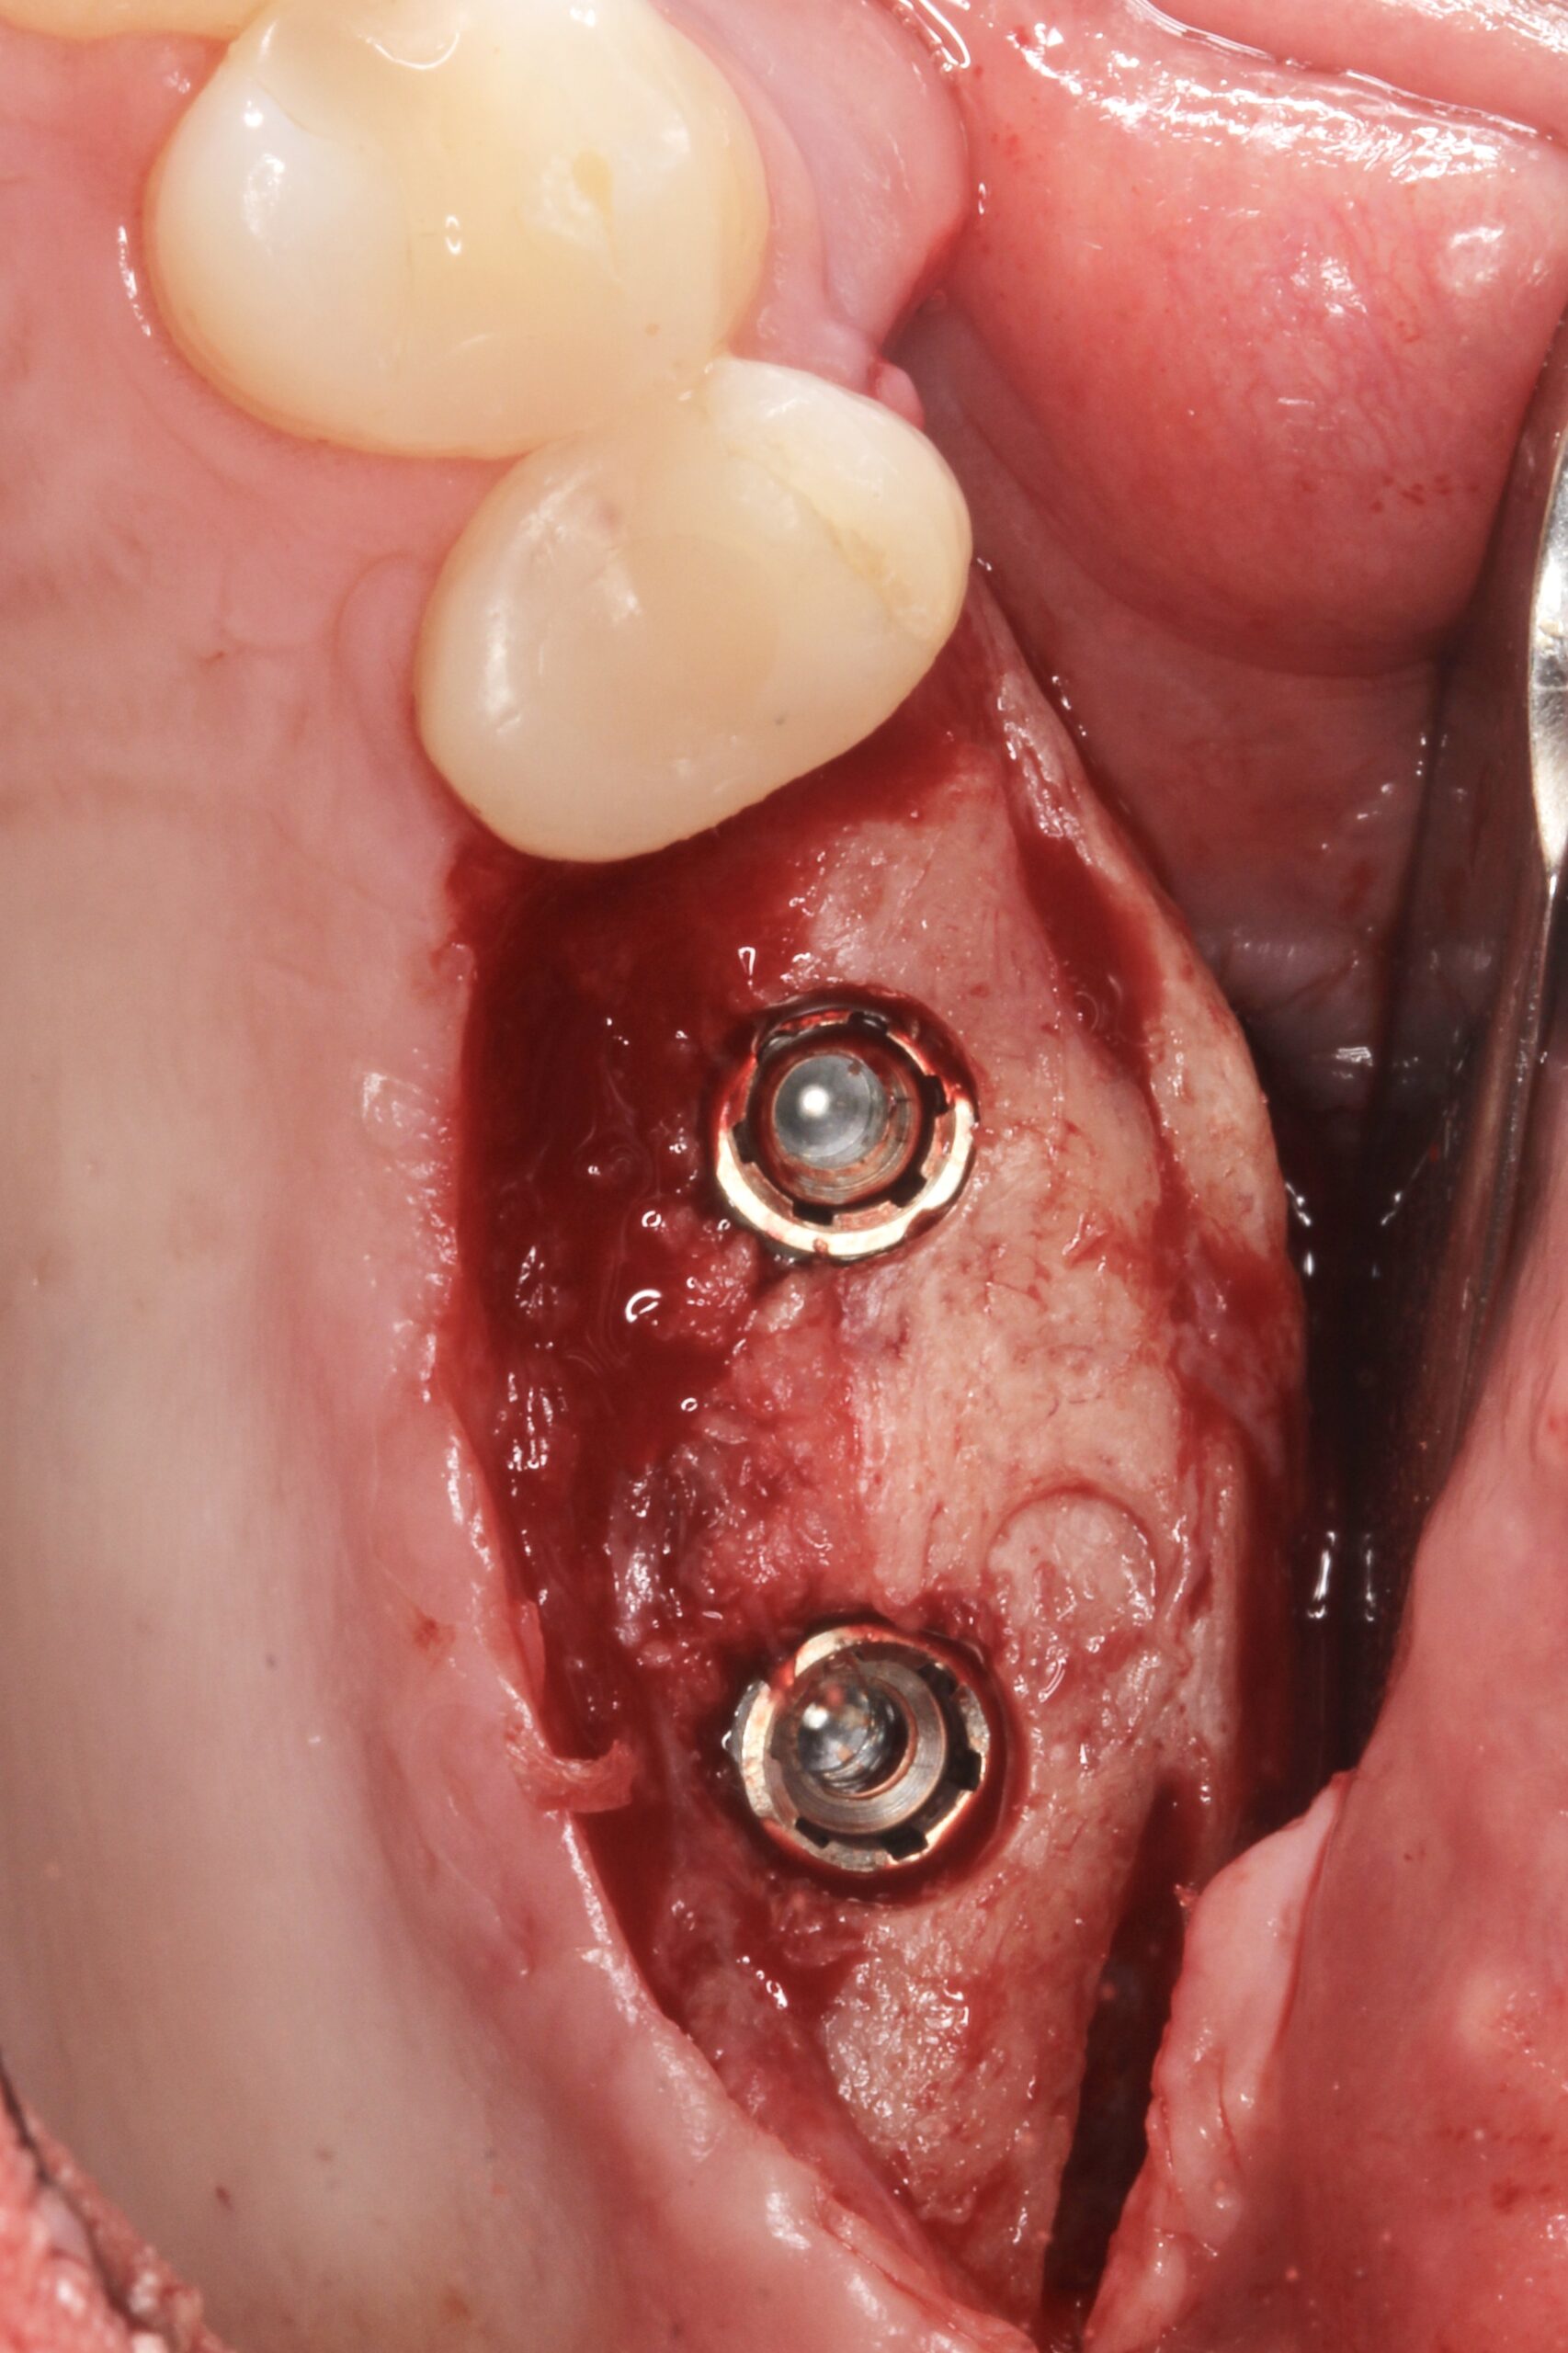

Figure 14.

Occlusal view of the implants.